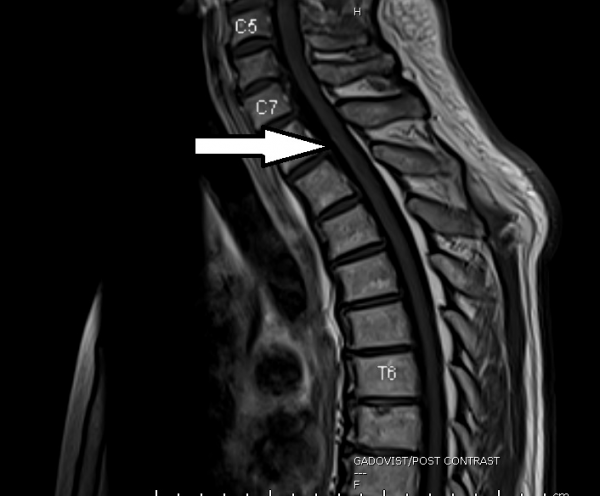

接下来,我给威叔做了详细的全身扫描,经过一连串的检查后,排除了老化、骨折、肿瘤、癌症转移等可能性,我就把他转到内科专科,由神经科与内科医生陈伟阳接手,继续寻找病因。

陈医生诊断威叔患了神经脊髓炎(Longitudinal extensive transverse myelitis,简称LETM),这是一种自身免疫性疾病,会造成神经性疼痛,肌肉无力,膀胱和肠道出现功能障碍等。